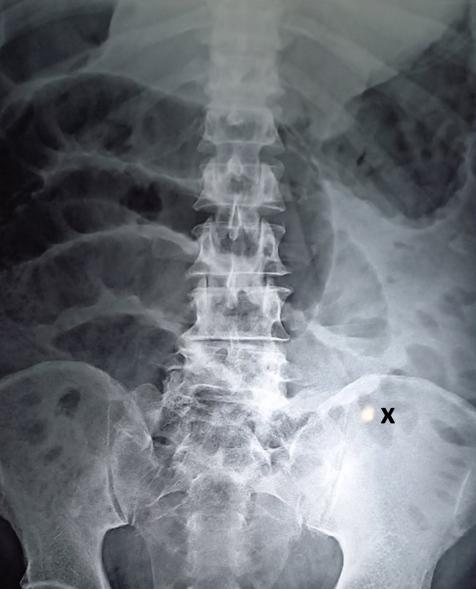

Suspecting he was going into septic shock, medics rushed the man to intensive care, where scans revealed that his abdomen was filling with fluid. This symptom suggested that his kidneys had stopped working — a possible sign of sepsis, where the body’s immune system attacks its own organs.

A subsequent two-hour operation revealed a small hole in his intestine, which the medical staff discovered was caused by an 0.8-inch-long fishbone. However, the farmer didn’t recall ingesting the 2-centimeter shard, the Daily Mail reported.

Nonetheless, the seemingly innocuous bone fragment had reportedly perforated his bowel, causing fecal matter to seep out and infect his abdominal wall. As a result, the intestine ballooned in size while yellow pus accumulated around the hole.